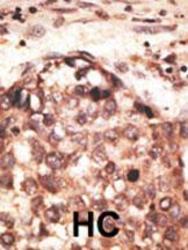

Supportive validation

- Submitted by

- Abcepta (provider)

- Main image

- Experimental details

- "Formalin-fixed and paraffin-embedded human cancer tissue reacted with the primary antibody, which was peroxidase-conjugated to the secondary antibody, followed by AEC staining. This data demonstrates the use of this antibody for immunohistochemistry; clinical relevance has not been evaluated. BC = breast carcinoma; HC = hepatocarcinoma."

- Primary Ab dilution

- 1:50~100